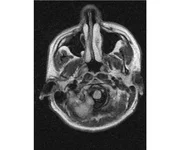

делал в обласной на siemense.В заключении выданом мне через 15мин.после мрт (легкая дегидрация)

Меня смутил факт выдачи заключения через 10мин(наверно они у них зарание напечатаные)я не медик.достаточно мимолётного взгляда на снимки?А вы видете на них гидроцефалию? Я лиш спросил куда идти с результатами томографии?и не хотел никого роздражать.

Я попросил взглянуть на снимки и сказать видна.ли на них гидроцефалия?или куда обратится за консультацией по этому вопросу?В мрт снимках наверно розбирается любой нервопатолог(я так предположил)

Я уже говорил, что независимо от того, есть на МРТ гидроцефалия или нет, лечиться тебе нужно только в том случае, если есть какие-либо проявления болезни, иначе на все эти анализы можешь забить... Но давай все-таки разберемся с томограммой.

Итак, с самого начала томограмма обозначала срез какого-либо органа на определенной глубине, позволяла заглянуть вовнутрь. При компьютерной томографии аппарат делает десятки срезов головного мозга в разных направлениях и из этого множества срезов он моделирует полноценное объемное изображение мозга в натуральную величину. Обрати внимание, компьютер работает не с этими миниатюрными изображениями, а с трехмерной моделью в масштабе 1:1. Эту модель вдоль и поперек анализирует суперсовременный компьютер, выполняющий миллионы операций в секунду. Только ***** может пытаться перепроверить компьютер, ведь человеку не хватит всей жизни чтобы проанализировать то, что компьютер с тобой сделал за 10 минут. Я хочу, чтобы ты это понял!

Ты разместл здесь несколько миниатюр и хочешь, чтобы врач по ним создал полноценное объемное изображение в натуральную величину, а потом осмотрел его со всех сторон и дал заключение? Но ведь это невозможно. Это просто насмешка над врачом, это издевательство над здравым смыслом. Принеси Букеру уменьшенный в 50 раз снимок зуба и спроси у него, в каком состоянии там корневые каналы. Или давай я дам тебе скрин со спутниковой карты города и попрошу тебя описать, какого цвета и какой модели запечатленная со спутника машина, какой у нее гос.номер, сколько в ней пассажиров, сколько из них мужчин и сколько женщин...

Надеюсь, ты понимаешь, что это невозможно. И воссоздать по приведенным тобой аватарам полную картину мозга тоже невозможно. Пойми, если уж называть вещи своими именами, то ты запостил полнейшую ***ню! Ты не хотел никого обидеть, ты ведь сам не ведал, что творил. Ты продемонстрировал полнейшую медицинскую безграмотность и полное невежество, но претензий к тебе нет. Ты ведь не один такой. Ты пожелал того, что сделать невозможно, и тут же у тебя нашлась сочувствующая, некая П., которую, по большому счету, надо бы послать в П., коль уж она считает, что врач должен тут сделать немедленно и бесплатно то, что делает немецкий компьютерный томограф ценой в миллионы долларов.